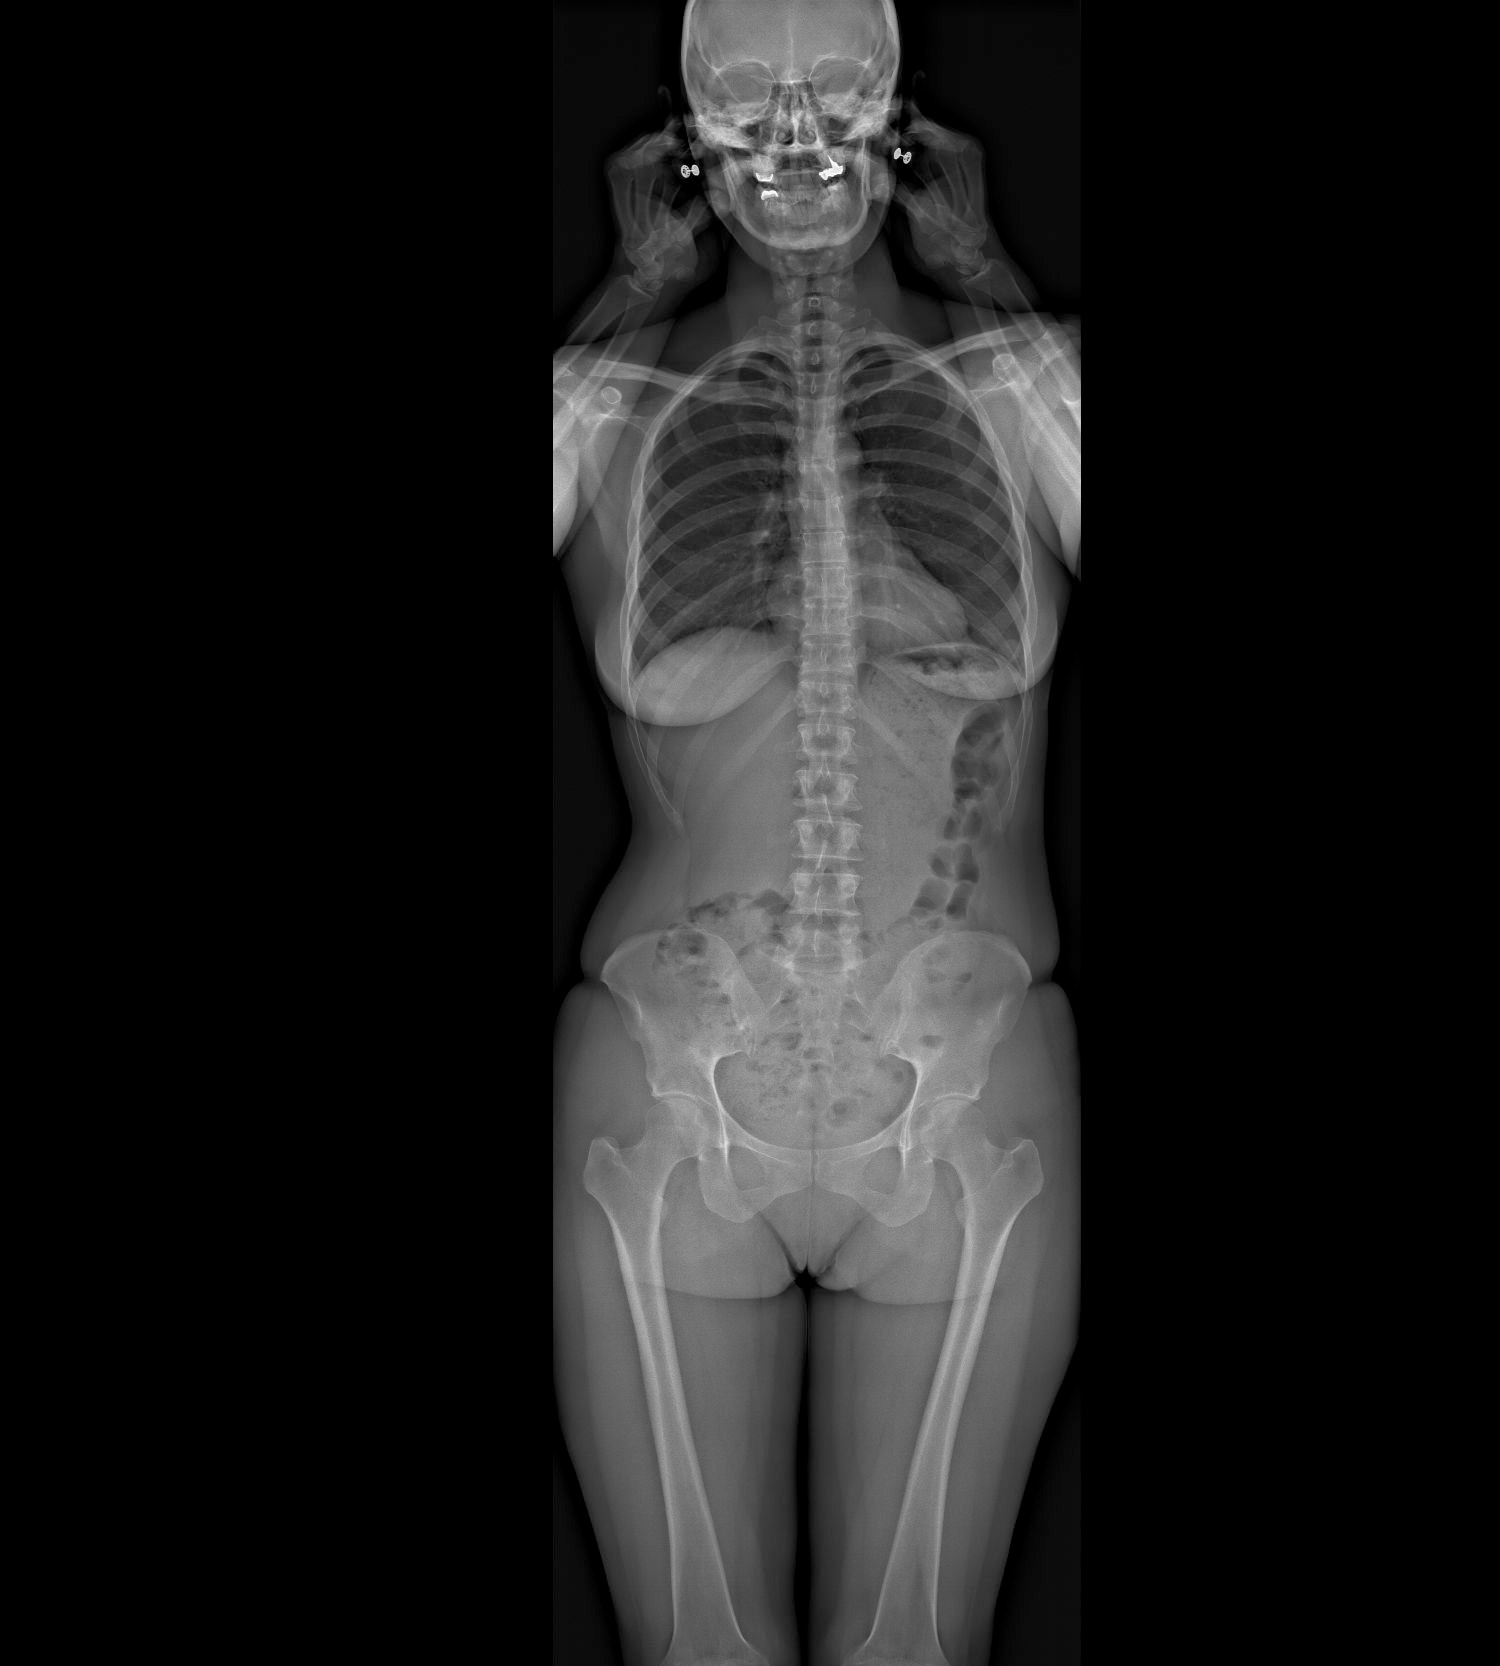

Ce système permet la réalisation de radiographies du corps entier en position debout, en une seule acquisition, sans assemblage d’images et sans distorsion verticale. Des clichés numériques de face et de profil, de tout ou partie du corps, sont obtenus simultanément avec une qualité d’image exceptionnelle et sans aucun agrandissement, garantissant une fiabilité parfaite des mesures.

À la manière d’une photocopieuse, un très fin faisceau de rayons X balaye le corps du patient de la tête aux pieds, réalisant une image de face et une de profil en quelques secondes et de manière simultanée. L’extrême sensibilité des détecteurs développés par Georges Charpak permet cette acquisition corps entier avec une dose de radiation 9 fois inférieure à celle des méthodes radiologiques classiques et jusqu’à 100 fois inférieure à celle d’un scanner.